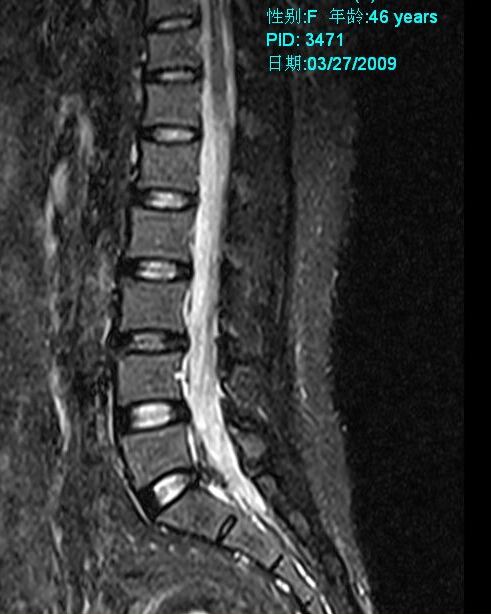

标题: MRI2099:此病人加做压脂像确诊为:终丝脂肪浸润。 [打印本页]

标题: MRI2099:此病人加做压脂像确诊为:终丝脂肪浸润。

此病人加做压脂像:腰1、2椎体平面椎管内条状高信号病灶信号明显降低。以下为压脂像图像: